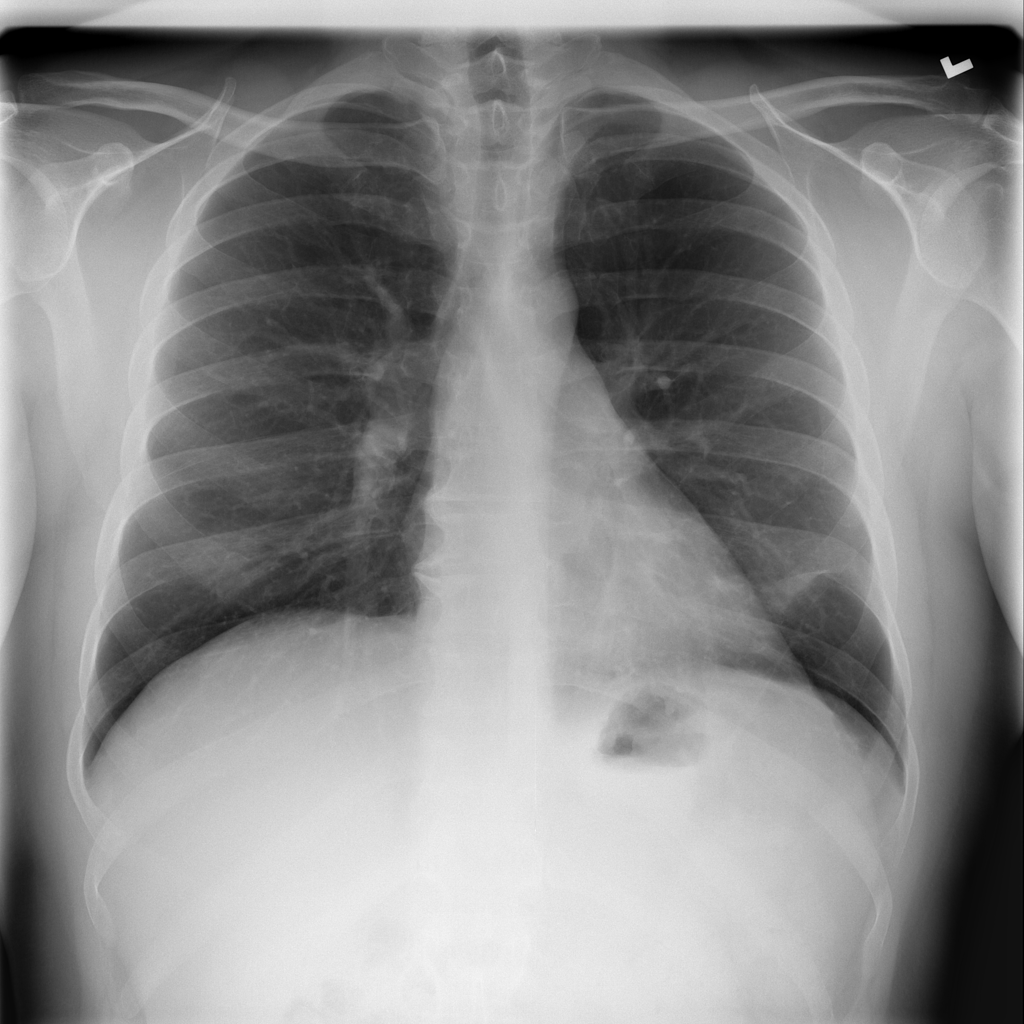

Consolidation

Consolidation refers to air-space filling that makes part of the lung appear denser on imaging.

Showing up to 90 reference images for Consolidation.

PAT-B733 · IMG-000Consolidation

PAT-B733 · IMG-000

PA